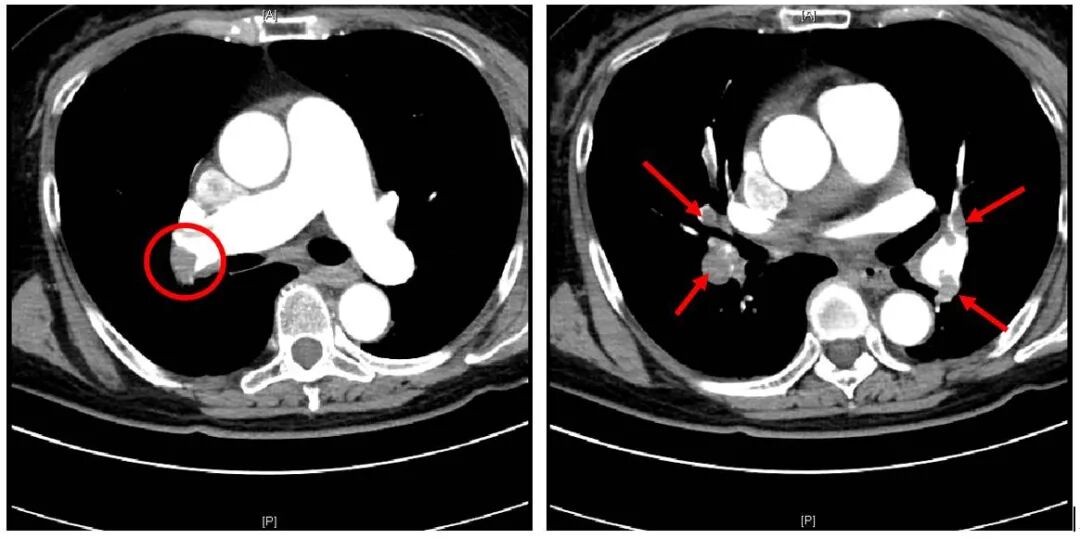

右肺动脉看到充盈缺损影!什么意思?就是说,造影剂流过肺动脉时,有一部分区域是没有造影剂的,造影剂绕过去了。为什么呢?只有一个解释。那就这里有血栓堵着。血栓不能直接在CT上显影。但是造影剂可以显影。正常的血管会充满造影剂,如果某一个区域没有造影剂,那就基本可以断定,这个位置被血栓霸占了。

(注:红圈及箭头所指,都是充盈缺损影,都是血栓,堵住了肺动脉,非本病人)